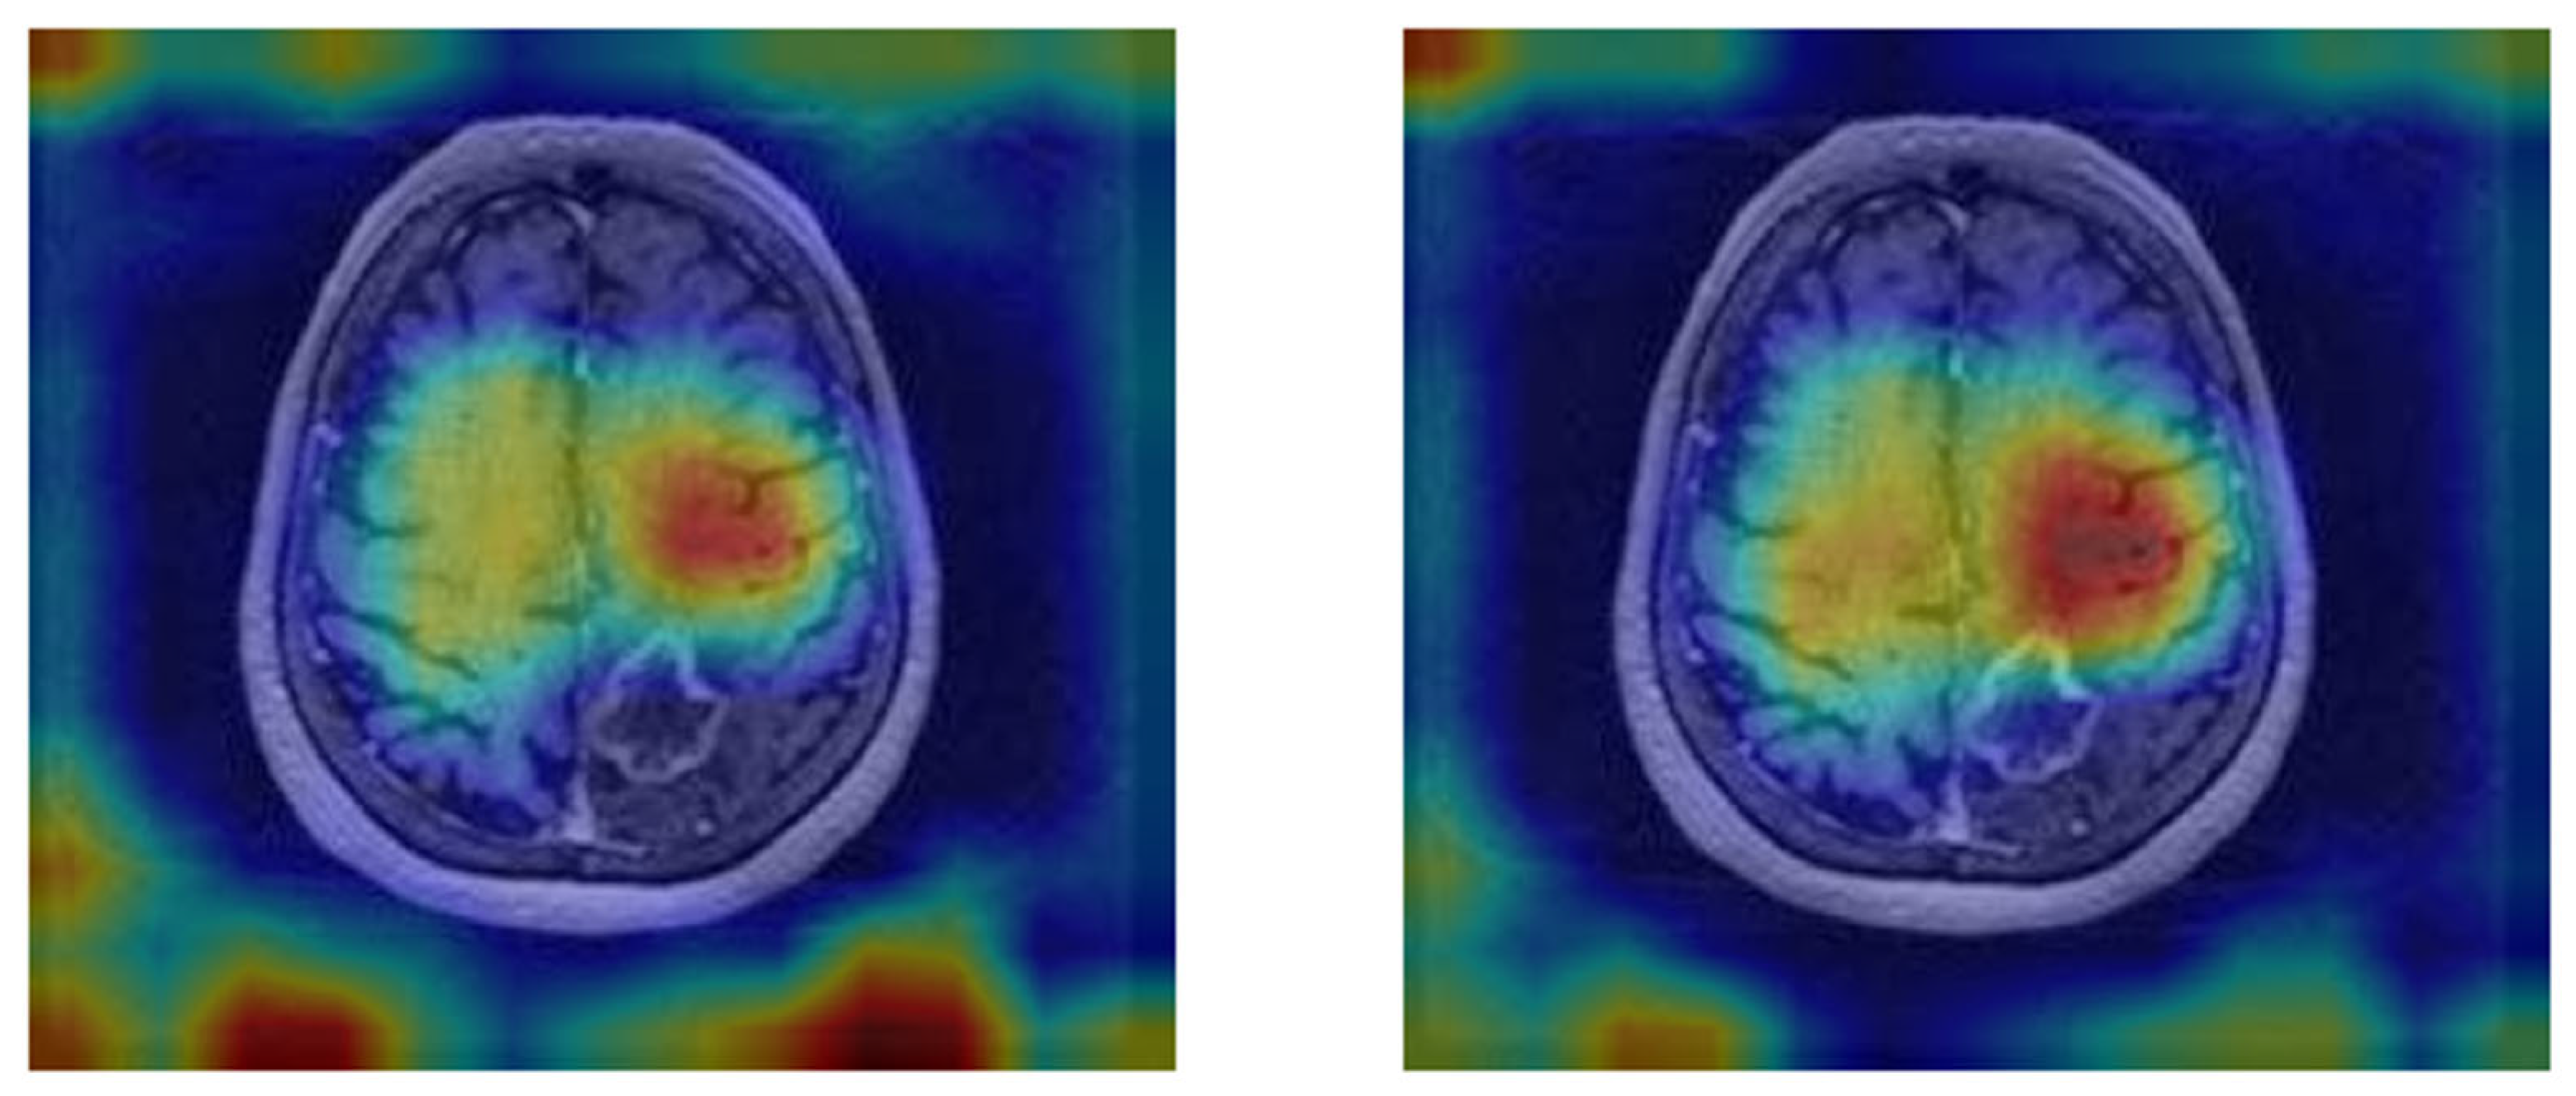

3.3. Qualitative Analysis

The vision transformer (ViT) model demonstrated the ability to focus on key tumor-related features, as shown by the attention maps in Figure 7. In the MRI images, distinct tumor regions are visible, characterized by altered enhancement patterns and edema surrounding the lesion. The corresponding attention maps reveal that the model consistently highlights patches associated with these abnormal regions.

The attention maps indicate that the model assigns higher attention (marked by warmer colors like red and yellow) to areas likely containing tumor tissue, suggesting it recognizes significant pathological features. This interpretability reinforces the clinical relevance of the ViT model, as it not only distinguishes tumor areas effectively but also aligns its focus with known tumor characteristics, aiding in understanding the basis of its predictions. These examples illustrate the model’s capacity to differentiate response patterns in brain metastasis, potentially contributing to improved diagnostic confidence in clinical settings.

Figure 7. MRI images with the attention maps superimposed.

Tomography 11 00015 g007